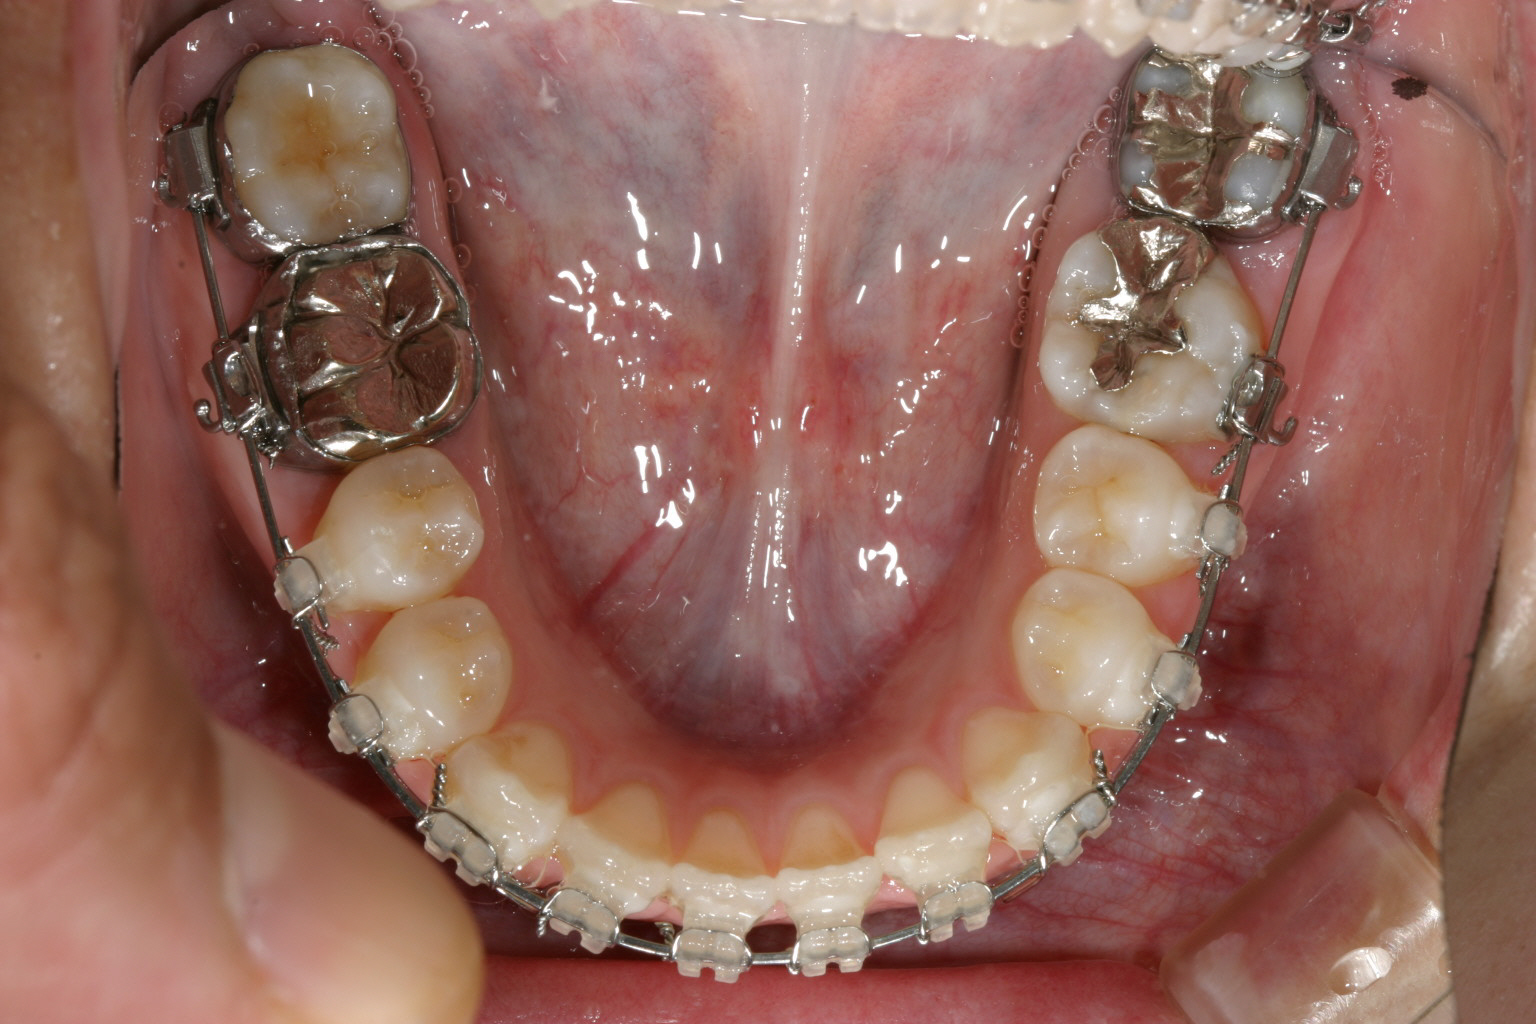

下顎も半年経つとかなり綺麗に並んでいます。

前歯部の開咬も殆どふさがってきています。 正中もピッタリです。 少し受け口傾向の為エラスティックを利用しました。 その為下顎前歯の犬歯のところに下向きの角が見受けられます。

下顎もバッチリです。

そのまま前歯を引っ張ったんじゃ後戻りを生じさせる可能性があるからです。